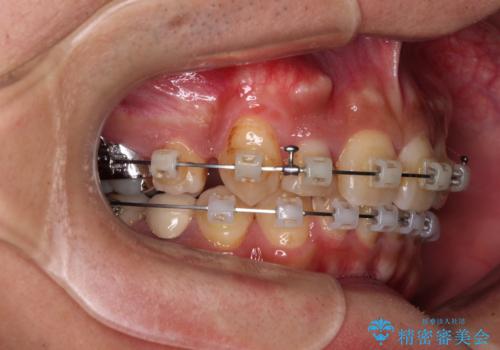

【モニター】八重歯と正中のずれた歯列 片顎抜歯のワイヤー矯正

- クリアブラケット

- 上顎の八重歯と正中のズレを気にして来院された患者様です。

八重歯による叢生は著しく、それにより上顎の正中が大きく右にずれている状態でした。

口元の突出感は感じていなかったことと、奥歯の咬み合わせを考慮し、上顎のみ左右の第一小臼歯を抜歯してワイヤー装置にて矯正治療を行うこととしました。

補助装置を併用することで効率的に八重歯や正中位置の改善を達成することができました。